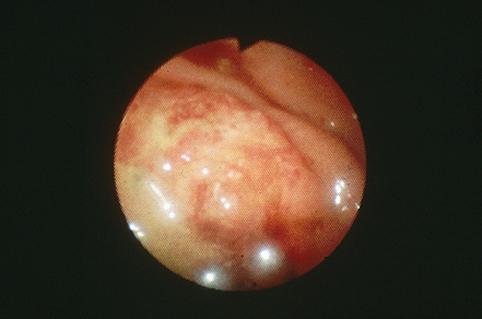

질환(병리주체)의 분류 악성 상피성종양/선암

부위(장기별) 대장/S상

검사방법 내시경

종양의 육안분류 3형(궤양침윤형)/

종양의 최대경(밀리미터) 40이상

종양의 심달도 ss(a1)